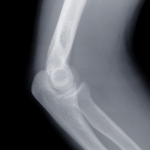

Bei Knochenbrüchen, Knochenkrebs, degenerativen Gelenkerkrankungen und Abnutzungserscheinungen können Defekte im Bereich von Knochen und Knorpel, sog. osteochondrale Defekte, entstehen. Diese Defekte verursachen in der Regel Schmerzen und erhebliche Bewegungseinschränkungen.

Eine Spongiosaunterfütterung ist dann angebracht, wenn durch den entstandenen Defekt die Stabilität des Knochensystems nicht mehr gegeben ist, weil der Körper die offene oder kranke Stelle im Rahmen der Selbstheilungskräfte nicht von alleine schließen oder heilen kann. Das betrifft vor allem die Grenze zur Knorpelschicht an dem betroffenen Knochen. Knorpel wird im Gegensatz zum Knochen vom Körper nicht selbst repariert. Typische Stellen wo solche Defekte vorkommen, sind das Knie- und das Hüftgelenk sowie das Sprunggelenk. Das sind auch die am stärksten beanspruchten Gelenke. Wenn nun in Knorpelnähe der Knochen schwammig wird, kann es sein, dass das Gewebe innerhalb des Knochens regelrecht verfault. Man spricht auch von Nekrose.

Das nekrotische oder abgestorbene Knochengewebe erfüllt keinerlei Funktion mehr und könnte das gesunde Gewebe in Mitleidenschaft ziehen. Dabei könnte der Knochen regelrecht brechen und das ohne jede Gewalteinwirkung. Also muss das nekrotische Gewebe minimalinvasiv entfernt werden. Minimalinvasiv heißt, dass durch einen kleinen Hautschnitt ein Kanal bis zum Defekt hergestellt wird, durch diesen Kanal lassen sich Sonden und Instrumente einführen. Die Sonden sind wichtig, damit der Operateur auf einem Bildschirm genau verfolgen kann, wo er sich gerade befindet und wie groß das Ausmaß des betroffenen Gebietes ist. So kann er mit einem scharfen Löffel das betroffene Gebiet bis hin zum gesunden Gewebe aushöhlen. Diese Höhle wird anschließend wieder aufgefüllt. Je nach Größe erfolgt dies mit Knochenmaterial, was zuvor dem Beckenkamm entnommen wurde und dem Material was beim Anbohren des betroffenen Areals an gesunden Material, bis hin zum Defekt entnommen wurde. Die verwendete Knochensubstanz wird als Spongiosa („Schwamm“) bezeichnet.